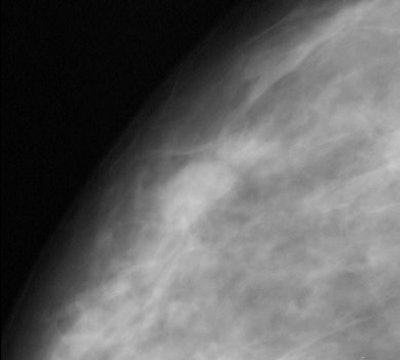

| Fifty-eight-year-old woman who presented with "pulling" on the inner left breast, diagnosed with bilateral invasive ductal carcinoma after biopsy. Above is the craniocaudal view mammogram. Cancer in left breast at point of clinical finding is apparent. A second cancer (arrow) was detected in the right breast. Butler SA, Gabbay RJ, Kass DA, Siedler DE, O'Shaughnessy KF, Castellino RA, "Computer-Aided Detection in Diagnostic Mammography: Detection of Clinically Unsuspected Cancers," (AJR 2004; 183: 1511-1515). |